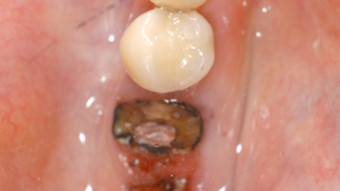

Dry Socket Pictures | Pictures of Alveolar Osteitis